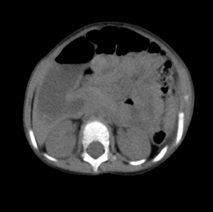

Abdominal ultrasound was normal with no hypertrophic in the pylorus. Barium enema was normal that exclude Hirschsprung disease. Abdominal X-ray showed expansion in the stomach with malposition of gases (Figure 1). Esophagogastroduodenoscopy (EGD) was performed that showed severe duodenal expansion at segment 2 followed by severe narrowing and inability to cross. An abdominal computed tomography scan (CT) showed the annular pancreas surrounding segment 2 of the duodenum (Figure 2). The patient did not have associated anomalies of the annular pancreas (Echocardiography, ECG, and abdominal ultrasound did not show any anomaly). The patient underwent surgery, an incomplete annular pancreas with duodenal stenosis in the second portion of the duodenum was observed. Duodenojejunostomy was performed (Figure 3a, 3b). The postoperative course was uncomplicated, and oral feeding was tolerated from the fourth day. The patient was discharged from the hospital on the 8th day after the operation. On follow-up, the patient was asymptomatic with normalweightgain.

Figure 1 Abdominal X-ray showed expansion in the stomach with malposition of gases.